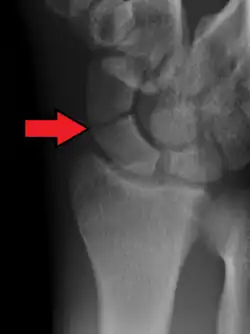

A more obvious scaphoid fracture on a scaphoid view X ray -